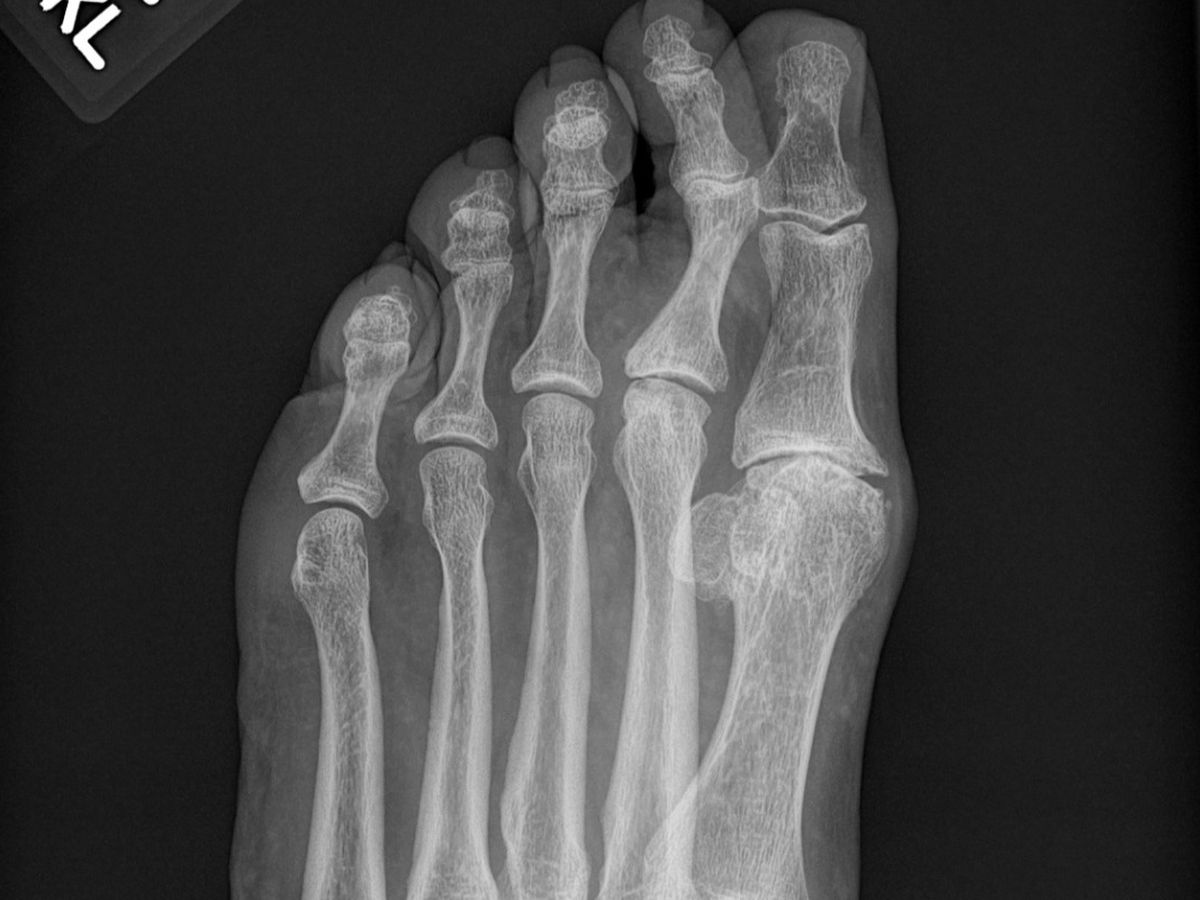

Some years ago I suffered an injury to the joint at the base of the big toe on my left foot. This occurred while I was undergoing alternative treatment for anxiety. The practitioner gave me a tension relieving massage treatment during which she pulled on each on my toes. When she pulled gently on my big toe I felt a small, sharp jolt of pain, and felt a corresponding internal "pop". From that moment on I had tenderness and a slight discomfort in that toe joint. I know she didn't mean to hurt me. And, at the time I could never have imagined that that little pain would become an excruciating nightmare down the road. I was uninsured at the time of the injury, but two years later, when I could go to a regular doctor again, I told him about the pain, but he brushed it off as nothing. As the years passed, the pain steadily grew until finally I saw a foot surgeon and he told me that the joint had degenerated and was arthritic. He recommended surgery to fuse the bone. That was five years ago, and I've been trying to scrape together the money to cover my deductible and co-pay ever since. I went back to the same surgeon this past May and fresh x-rays reveal that not only is the big toe joint much worse, the toe next to it is being effected by the growing deformity as well. I'm insured under Obamacare, but every year my premiums, deductible and co-pay get higher and I just can't raise this money myself. If it was just a matter of this bill alone, I would pay it in installments no matter how long it took. But, unfortunately I'm already swimming in $18,000 of medical debt and I just can't squeak out another payment. I've read numerous stories of people raising funds for all sorts of this on this site, so I thought I'd try it.